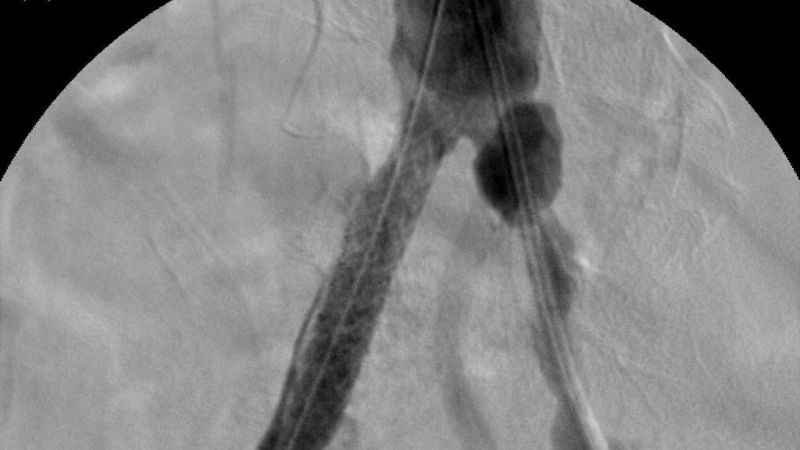

Türkiye’nin ilk yerli stent grefti başarıyla hastalara uygulandıINVAMED'in geliştirdiği "Atlas Stent Greft", Bezmiâlem Vakıf Üniversitesi Tıp Fakültesi'nde gerçekleştirilen başarılı operasyonla hastalara uygulandı.

Özellikle anjiyografik yöntemlerle ameliyat gerektirmeden tedavi olanağı sunuluyor. Balon, stent ve damar tıraşlama yöntemleri, bu tedavilerin başında geliyor. Bu tedavilerde kullanılan tıbbi cihazların üretimi bir zamanlar yalnızca belirli ülkeler tarafından yapılırken, artık Türkiye kendi cihazlarını üreterek dünya sahnesinde yer alıyor. Bu alanda yaşanan en büyük yeniliklerden biri de "stent greft" teknolojisi oldu. Üretimi dünyada sadece 5 ülke tarafından yapılan stent greft üretimi ile Türkiye, tıbbi inovasyon alanında tarihi bir başarıya imza attı. Bu büyük adım Türkiye'nin sağlık teknolojilerindeki gelişimini küresel arenada da tescilledi.

Türkiye'nin ilk yerli stent grefti Bezmiâlem Vakıf Üniversitesi Tıp Fakültesi'nde Prof. Dr. Cengiz Köksal ve Doç. Dr. Emre Selçuk'un öncülüğünde Artven koordinasyonuyla bir hastaya başarıyla uygulandı. Doç. Dr. Emre Selçuk, bu büyük adımı şöyle değerlendirdi:

"Stent-greft teknolojisi, damar tedavilerinde kritik bir rol oynuyor. Damar balonlaşması veya yaralanma riski olan hastalarda bu teknolojinin önemi daha da artıyor. Artık bu teknolojiyi Türkiye'de üretiyor olmamız, operasyon başarımızı artırmanın yanı sıra, hasta güvenliğini de üst seviyelere taşıyacaktır. Türkiye'nin tıbbi alandaki bu başarısında yer almaktan büyük gurur duyuyoruz. Atlas Stent Greft, Türk mühendisliğinin ve Türk doktorlarının inovasyonunun ne kadar ileri seviyede olduğunun bir göstergesidir."